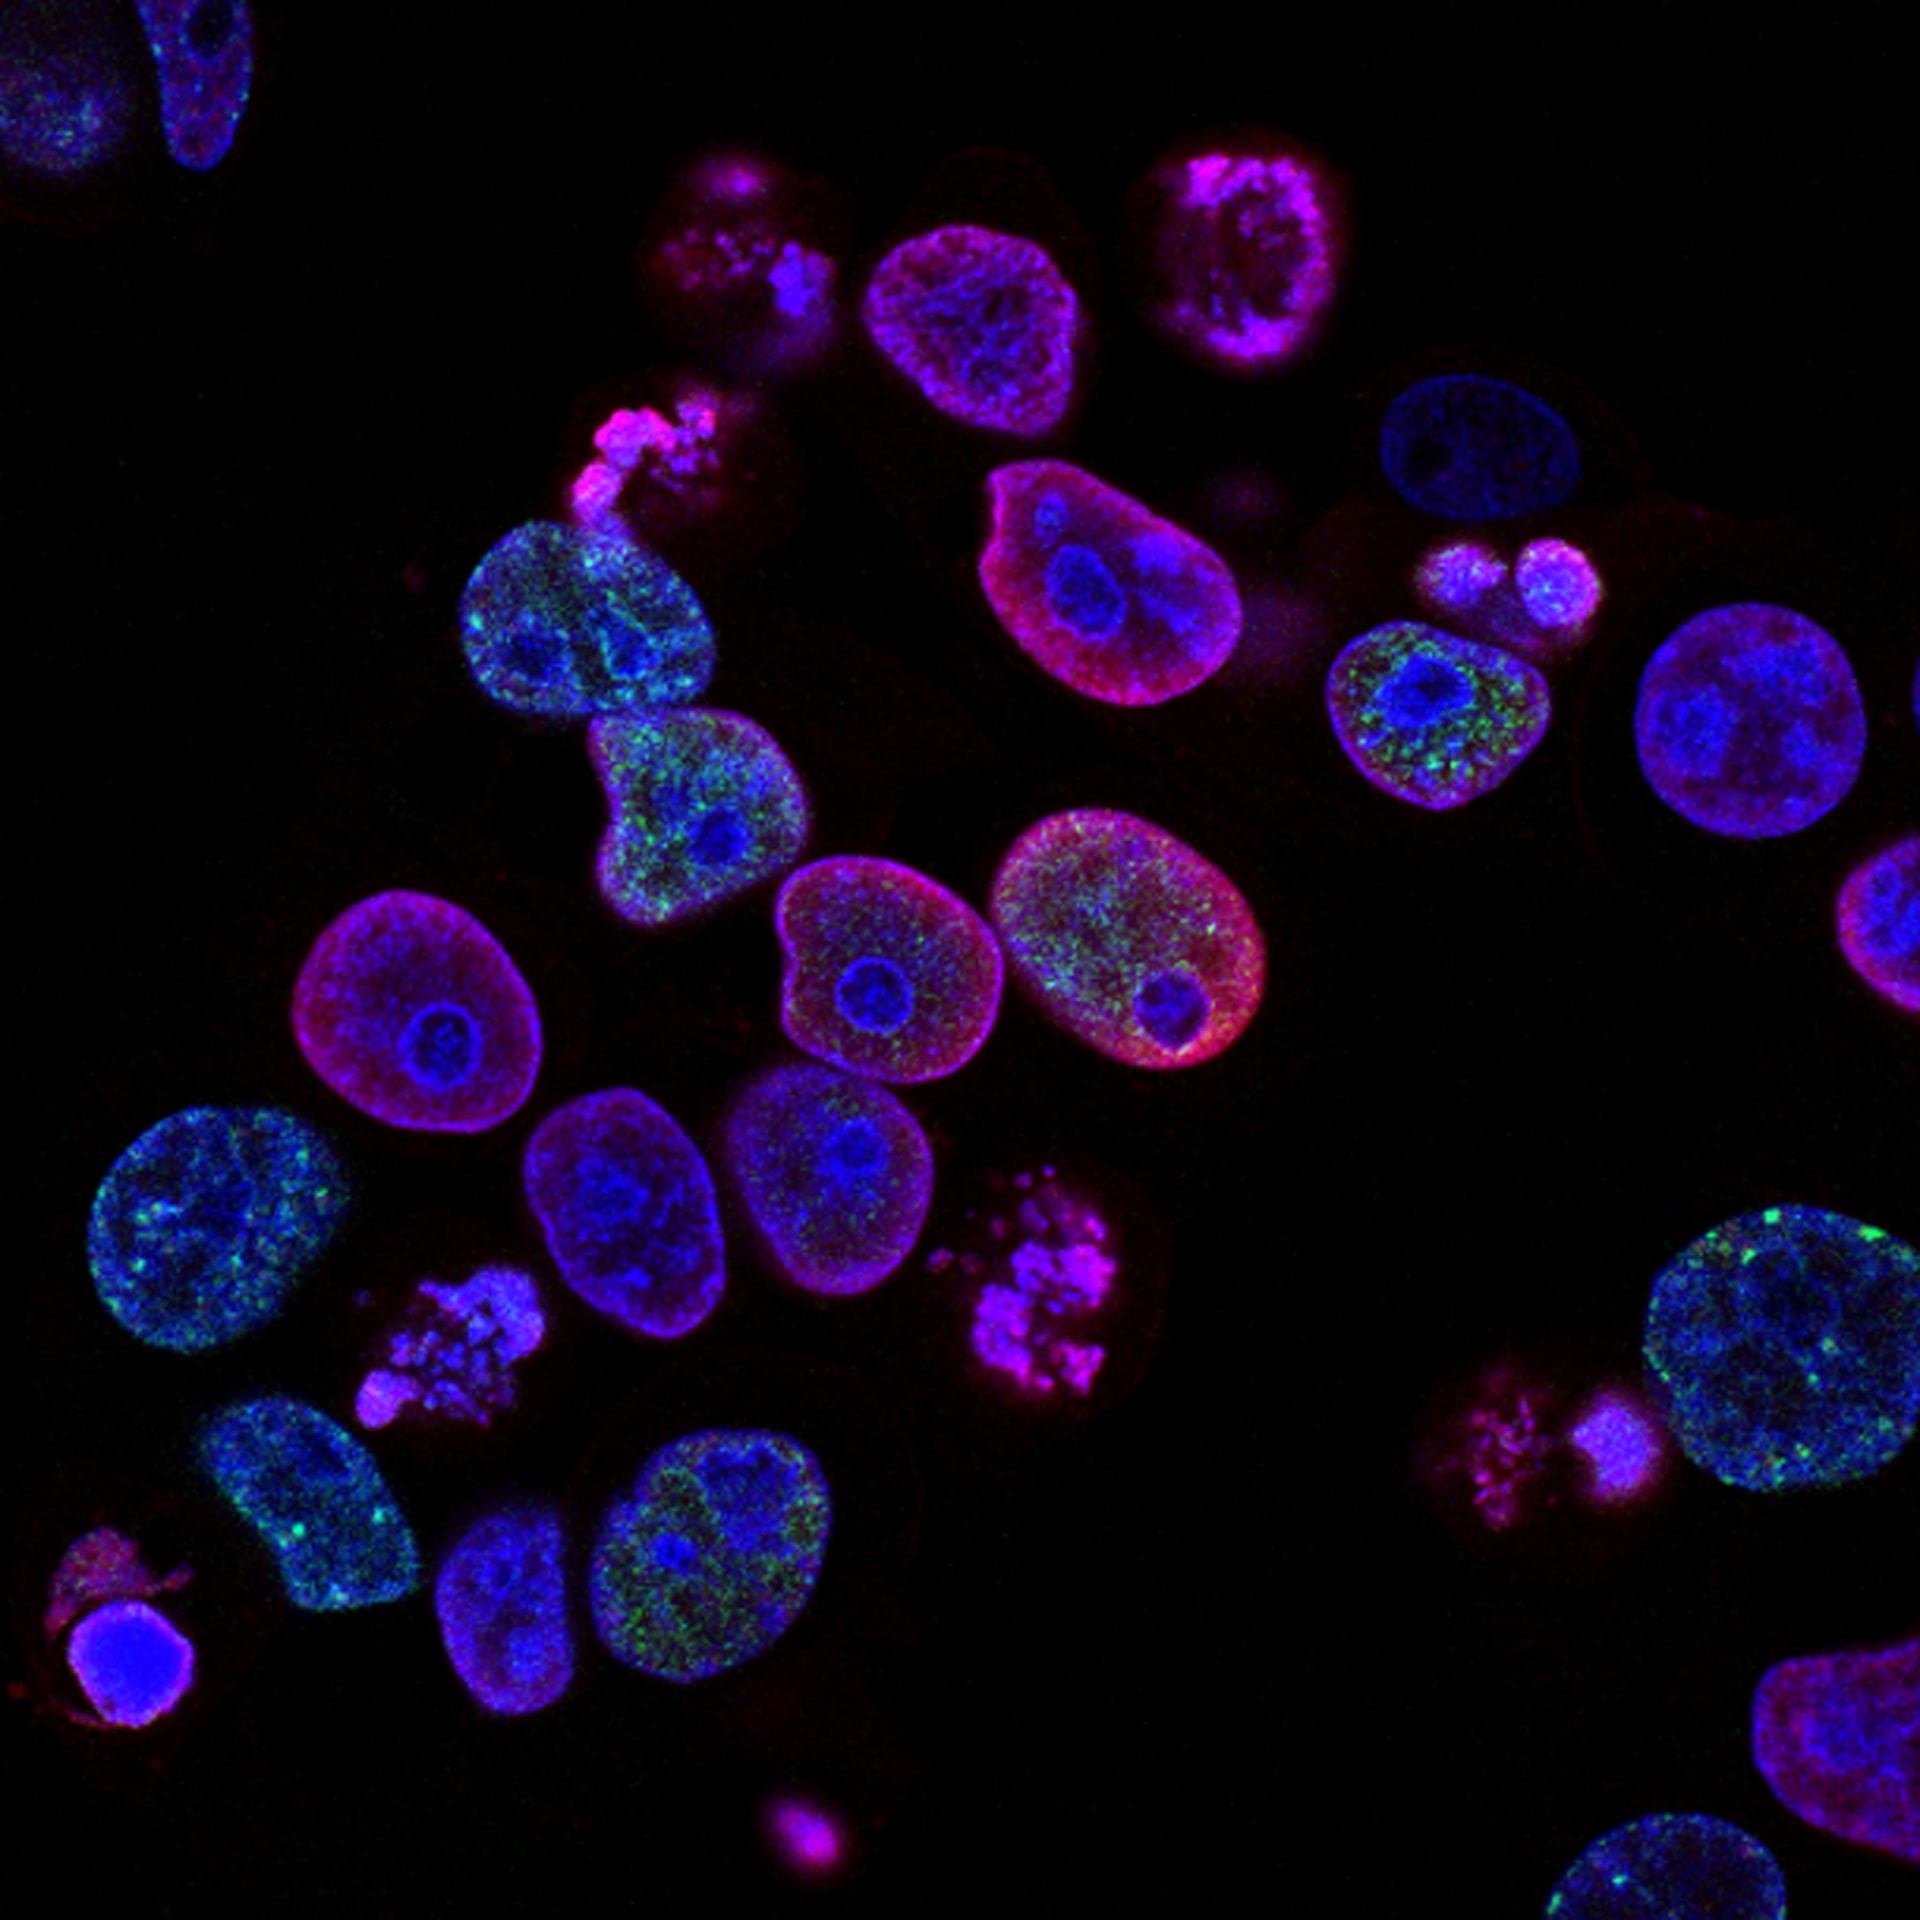

Eikon Therapeutics